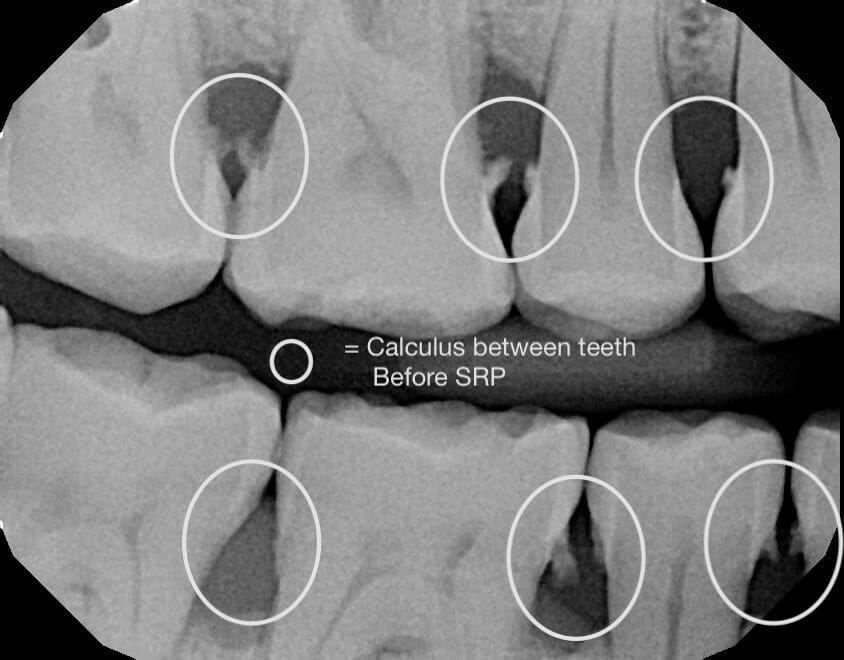

Scaling and Root Planing (SRP), which is commonly referred to as a deep cleaning or gum therapy, is the removal of plaque along with smoothing the roots of your teeth. And when patients who visit our office are diagnosed with gum disease, a deep cleaning is what we’ll recommend.

Some typical signs of gum disease that we most commonly see in the office are swollen and bleeding gums (especially while brushing), calculus near or below your gums, bad breath, and pain in your gums.

However, having one or many of these symptoms doesn’t mean that you can’t dramatically improve your oral health. Depending on the stage and severity of your condition, the deep cleaning you’ll receive at MFD – in combination with improved habits and oral hygiene that we’ll cover – can help you get back on the right path for your gums and teeth.